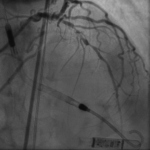

A 73-year-old man presented with angina chest pain. Stress MPI showed anterior and inferior ischemia while planning for lower limb vascular surgery. PMH: Extensive PAD s/p multiple PTAs, HTN, HLD,…